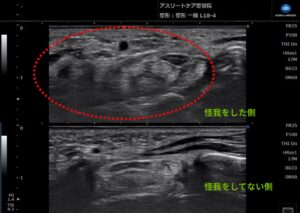

当院で**エコー(超音波画像観察装置)**を用いて詳しく観察したところ、手根管(神経の通り道)全体に強い腫れが確認できました。

原因を紐解くと、固定期間中に固定具がグラグラと動いてしまっていたことが判明しました。

固定具が手のひら側に当たり続け、二次的な被害として神経を圧迫し、炎症を引き起こしていたのです。